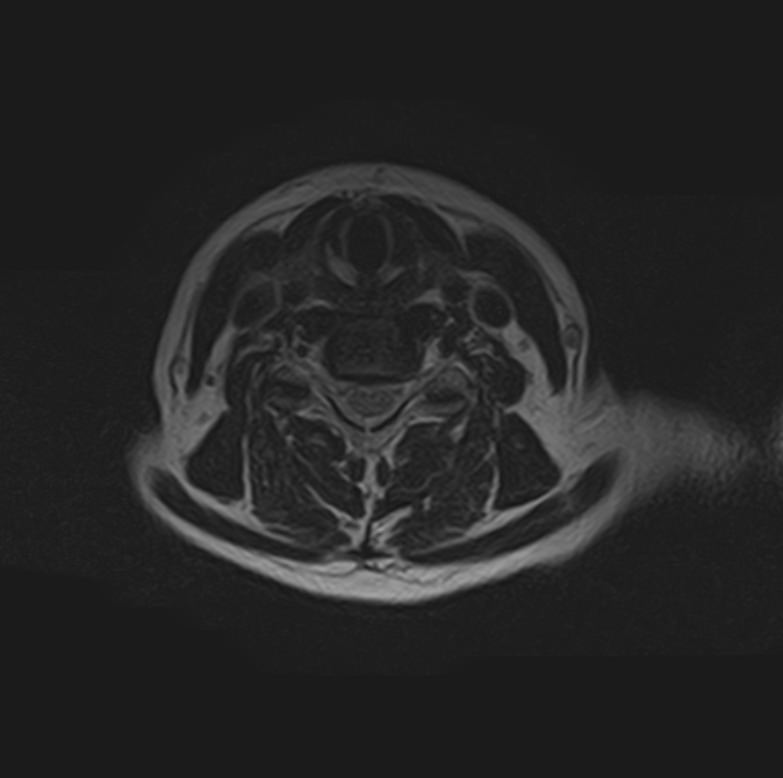

В клинике «Доступная медицина» можно пройти комплексное обследование, включающее в себя два протокола сканирования близко расположенных друг от друга анатомических областей – шейного отдела позвоночника и головного мозга.

Сканирование проводится на современном высокопольном магнитно-резонансном томографе закрытого типа TOSHIBA VANTAGE TITAN 1,5 Тесла, который делает послойные срезы в разных плоскостях с шагом от 1 мм и на основе полученных данных создает трехмерные изображения превосходного качества. Метод исследования позволяет в мельчайших подробностях визуализировать состояние всех структур головного мозга и шейного отдела позвоночника, что дает возможность выявлять патологические изменения на ранних стадиях и назначать своевременное лечение.